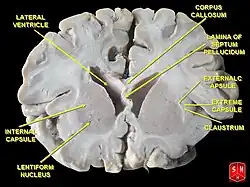

Aus dem unpaaren Hirnbläschen des Endhirns entwickelt sich ein Paar ungefähr halbkugelförmiger Gebilde, die Hemisphärenbläschen, die je zur Großhirnhemisphäre (Hemisphaerium cerebri) einer Seite werden. Neben der unpaaren medianen Gewebebrücke (Lamina terminalis) entstehen beide Hemisphären miteinander verbindende Querbahnen, die Kommissursysteme des Endhirns wie der breite Balken (Corpus callosum). Linke und rechte Hemisphäre werden durch eine tiefe Längsfurche (Fissura longitudinalis cerebri) geschieden und umschließen je einen Seitenventrikel als inneren Liquorraum. Jede der Hemisphären enthält innen gelegene Kerngebiete als Basalganglien (Nuclei basales), die aus dem ventralen (bauchseitigen) Telencephalon entstehen. Diese werden umhüllt vom außen liegenden Hirnmantel (Pallium), der aus dem dorsalen (rückenseitigen) Telencephalon hervorgeht.

Die Oberfläche des Palliums besteht als Rinde des Endhirns oder Großhirnrinde (Cortex cerebri) – ähnlich wie die Kleinhirnrinde (Cortex cerebelli) – aus Grauer Substanz mit Nervenzellkörpern in mehreren Schichten. Darunter liegt als sogenanntes Marklager aus Weißer Substanz ein dichtes Geflecht von Nervenfasern, deren Nervenzellfortsätze vielfältige Verbindungen schaffen. Als Assoziationsfasern verbinden sie unterschiedliche Areale des Cortex cerebri der Hemisphäre gleicher Seite untereinander, als Kommissurfasern mit solchen der Gegenseite und als Fasern von Projektionsbahnen stellen sie auf- oder absteigend Verbindungen von und zu verschiedenen anderen Regionen des Gehirns bzw. des zentralen Nervensystems dar.

Die beiden Hemisphären sind durch Fasersysteme gegenseitig miteinander verbunden, die als Kommissuren (Commissurae) die Medianebene queren; von diesen drei ist der Balken am faserreichsten:

Die aus dem ventralen Telencephalon hervorgehenden subkortikalen Kerne werden auch als basale Kerne oder Nuclei basales bezeichnet bzw. als Basalganglien. Sie liegen an der Basis des Endhirns seitlich und bauchseitig eines Seitenventrikels und schließen an Bereiche des Thalamus des Zwischenhirns. Infolge der hindurchziehenden Fasern von und zur Großhirnrinde hat ein Teil der Kerne ein gestreiftes Aussehen, weshalb diese auch als Corpus striatum (Streifenkörper) bezeichnet werden.